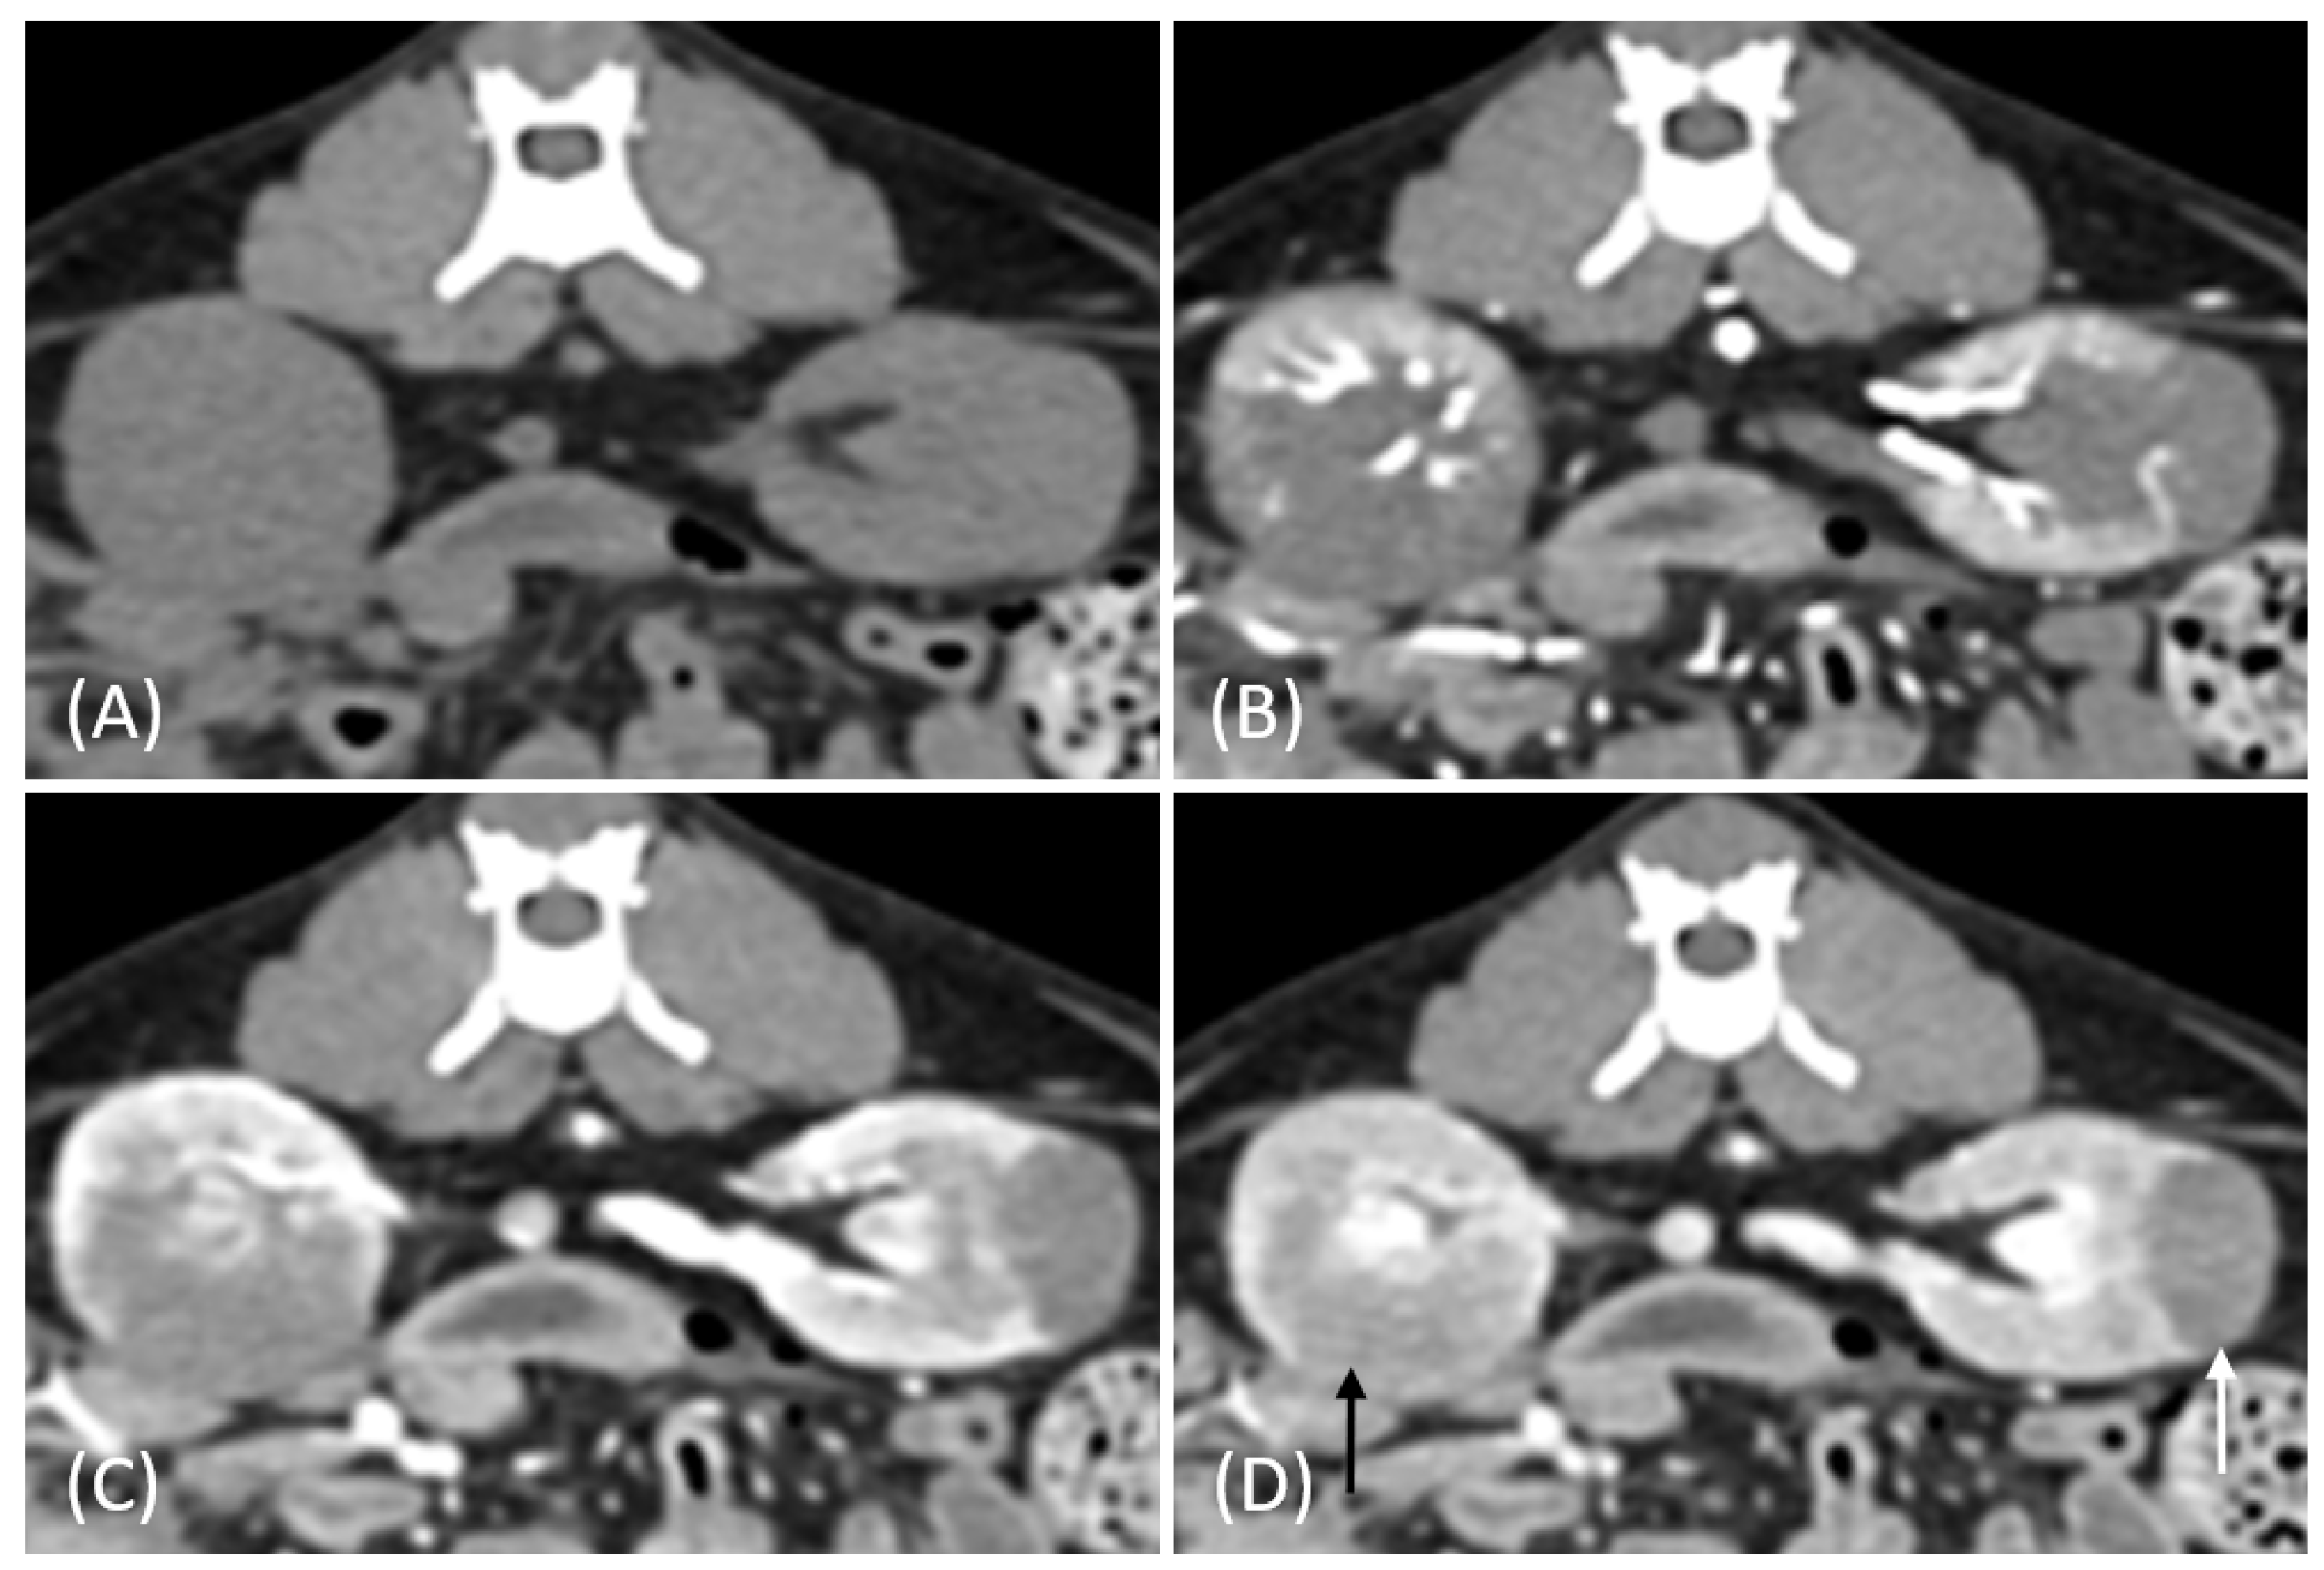

Figure 5.

(A) Pre-contrast, (B) corticomedullary phase, (C) nephrographic phase, and (D) delayed nephrographic/early excretory phase contrast-enhanced computed tomography (CT) images of a cat with primary renal lymphoma. The right kidney shows a unilateral, infiltrative mass with noticeable hypertrophy. The tumor is homogeneous and hypodense, displaying progressive enhancement.